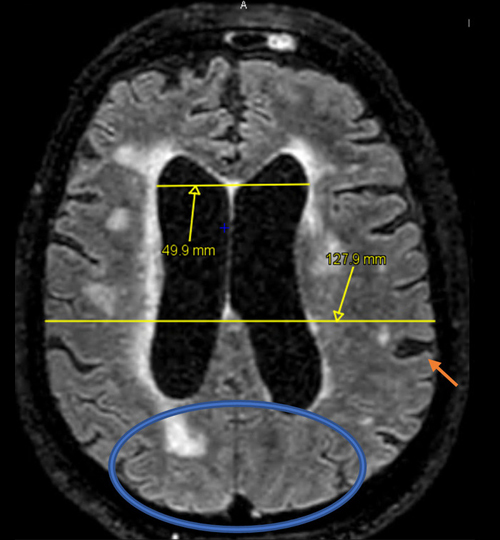

L’hydrocéphalie à pression normale (HPN) est une cause potentiellement réversible de troubles de la marche chez les patients âgés. Le diagnostic est difficile et plusieurs autres pathologies doivent être évoquées. Quand suspecter une HPN ? Quels examens réaliser ? Quelle prise en charge ? Quel suivi pour les patients porteurs d’une dérivation ?